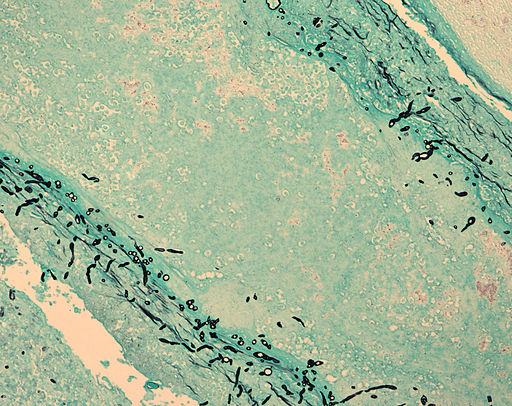

Recent studies revealed that Malaria can very well become drug resistant. Researhcers revealed that the parasite that causes the disease may react to medication for a certain amount of time, but might eventually develop resistance to it. READ MORE